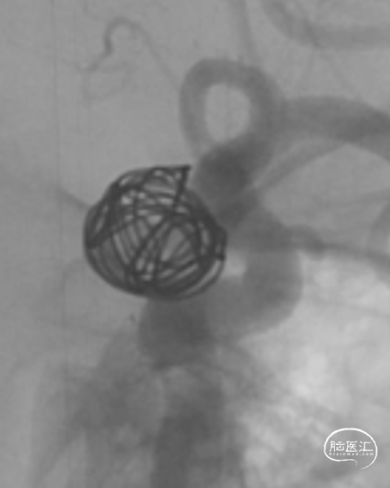

YonFlow®血流导向密网支架释放。

1、该例患者的大型动脉瘤位于左侧颈内动脉眼动脉段,瘤颈较宽(动脉瘤最大直径11.3mm,瘤颈8.5mm),且位于靠近虹吸弯的眼动脉段,给FD的选择带来一定困难;瘤颈近端与远端的载瘤血管直径差异较大(1mm),为保证支架充分贴壁,对支架的选择要求较高。术者选择应用一款可100%回收的钴铬合金材质的FD——YonFlow®血流导向密网支架,钴铬合金材质使得支架网丝相对镍钛更硬,释放后短缩程度小,尺寸选择相对容易,定位更精准。100%可回收的创新型设计使得支架在完全推出后依然可回收并重新精准定位,从而确保支架的良好贴壁。

2、支架网丝的远端为球形头端设计,可有效避免支架头端对血管壁及穿支的损伤,提高了支架输送及释放时的远端安全性。该款支架同时具备良好显影性,在透视情况下可完整体现支架的结构,使释放时的判断及调整更加可控。

4、本例术中如何实现FD精准定位,是手术最困难的一个技术点。YonFlow®FD独创的100%可回收功能可实现支架从微导管完全推出后仍能回收至微导管重释放,同时输送系统支架近端/远端还带有定位Mark点,这些均可帮助医生在术中的安全释放、精确定位和方便调整,使支架释放位置至最佳,从而进一步提升手术精准度和效果,增加手术的成功率和安全性。